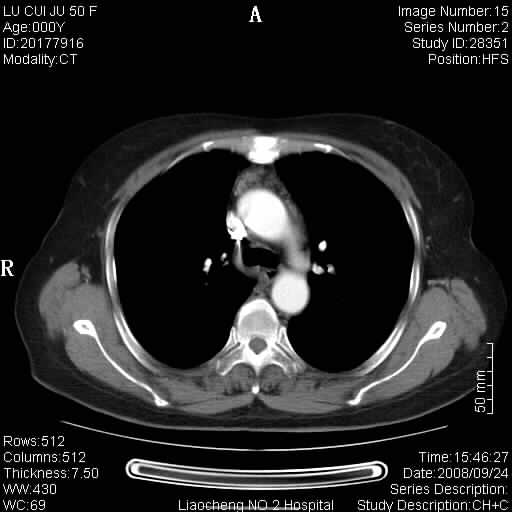

标题: CT15870:F50Y,纵膈占位,是不是胸腺瘤,请各位高手讨论。

临床表现为重症肌无力;ct增强扫描可见前纵膈胸腺部位弥漫性簇状软组织节结灶,不知道是不是胸腺瘤,请各位高手讨论。

胸腺外缘稍向外突,未见确切占位改变。结合临床考虑胸腺增生可能性大。

考虑胸腺增生!!

胸腺组织残留